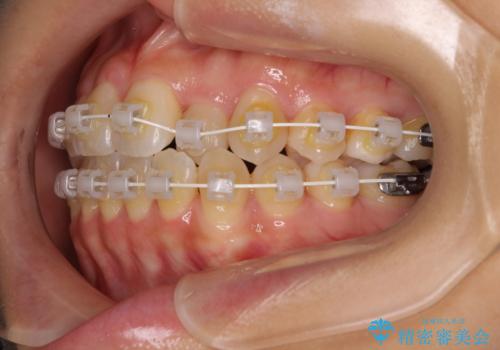

クロスバイトの前歯を改善 ワイヤー装置で楽々矯正治療

- 矯正装置

- 審美装置

- 1年4ヶ月

舌のトレーニングをしっかりと行っていただき、補綴治療も含めて1年強の短期間で治療を終えることができました。